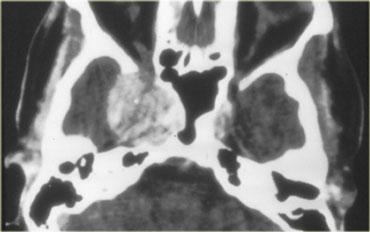

Và hình ảnh mặt phẳng ngang (axial).

CT không tiêm thuốc cản quang cho thấy các vôi hóa rõ ràng hơn.

Sau khi tiêm thuốc cản quang tĩnh mạch, toàn bộ phạm vi của tổn thương và các thành phần dạng nang của nó trở nên kém rõ ràng hơn nhiều.